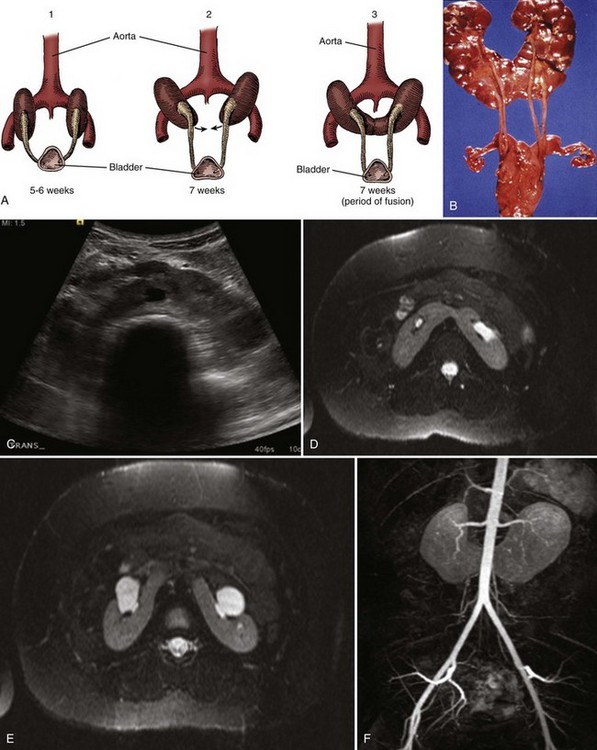

The horseshoe kidney is the most common of all renal fusion anomalies. It should not be confused with asymmetrical or off-center fused kidneys, which may give the impression of being horseshoe shaped. The anomaly consists of two distinct renal masses lying vertically on either side of the midline and connected at their respective lower poles by a parenchymatous or fibrous isthmus that crosses the midplane of the body. It was first recognized during an autopsy by Da Carpi in 1522, but Botallo, in 1564, presented the first extensive description and illustration of a horseshoe kidney (Benjamin and Schullian, 1950).

Horseshoe kidney occurs in 0.25% of the population, or about 1 in 400 persons (Dees, 1941; Nation, 1945; Bell, 1946b; Glenn, 1959; Campbell, 1970). A recent review of more than 15,000 radiologic imaging studies revealed an incidence of 1 in 666 individuals (Weizer et al, 2003). Horseshoe kidney is found more commonly in males with a ratio slightly greater than 2 : 1 (Basar et al, 1999; Weizer et al, 2003). The abnormality has been discovered in all age groups, ranging from fetal life to 80 years. In autopsy series, it is more prevalent in children (Segura et al, 1972). This early age prevalence is related to the high incidence of multiple congenital anomalies associated with the horseshoe kidney, some of which are incompatible with long-term survival (Scott, 2002).

Horseshoe kidneys have been reported in identical twins (Bridge, 1960) and among several siblings (David, 1974). It is doubtful that this anomaly represents a particular genetic predisposition, but it may be the result of a genetic expression with a low degree of penetrance (Leiter, 1972).

The abnormality occurs between the fourth and sixth week of gestation, after the UB has entered the renal blastema. In view of the ultimate spatial configuration of the horseshoe kidney, the entrance of the UB had to have taken place before rotation and considerably before renal ascent (Fig. 117–16). Boyden (1931) described a 6-week-old embryo with a horseshoe kidney, the youngest fetus ever discovered with this anomaly. He postulated that at the 14-mm stage (4.5 weeks), the developing metanephric masses lie close to one another; any disturbance in this relationship might result in the masses joining at their inferior poles. A slight alteration in the position of the umbilical or common iliac artery could change the orientation of the migrating kidneys, leading to contact and fusion. It has been postulated that an abnormality in the formation of the tail of the embryo or another pelvic organ accounts for the fusion process (Cook and Stephens, 1977). Domenech-Mateu and Gonzales-Compta (1988), after studying a 16-mm human embryo, suggested that posterior nephrogenic cells migrate abnormally to form an isthmus, or connection, between the two developing kidneys to create the horseshoe shape.

Figure 117–16 A, Embryogenesis of horseshoe kidney. The lower poles of the two kidneys touch and fuse as they cross the iliac arteries. Ascent is stopped when the fused kidneys reach the junction of the aorta and inferior mesenteric artery. B, Postmortem specimen showing horseshoe kidney with bilateral duplicated ureters. C, Ultrasonogram of horseshoe kidney at the level of the isthmus. D, MR urogram shows axial T2 fat-saturated image at the level of the isthmus. E, Axial T2 fat-saturated image demonstrates extrarenal pelves. F, Angiographic sequence shows variable blood supply to the kidney. G, Transverse ultrasonogram of 14-year-old girl with left flank pain found to have marked left hydronephrosis in a horseshoe kidney (arrow). H, MAG3 scan demonstrates left ureteropelvic junction obstruction. I, Coronal T2 images of MR urogram show the isthmus (arrow) and severe left hydronephrosis.

(A, From Benjamin JA, Schullian DM. Observation on fused kidneys with horseshoe configuration: the contribution of Leonardo Botallo [1564]. J Hist Med Allied Sci 1950;5:315, after Gutierrez, 1931; B, from Weiss, MA, Mills, SE. Atlas of genitourinary tract disorders. Philadelphia: JB Lippincott; 1988.)